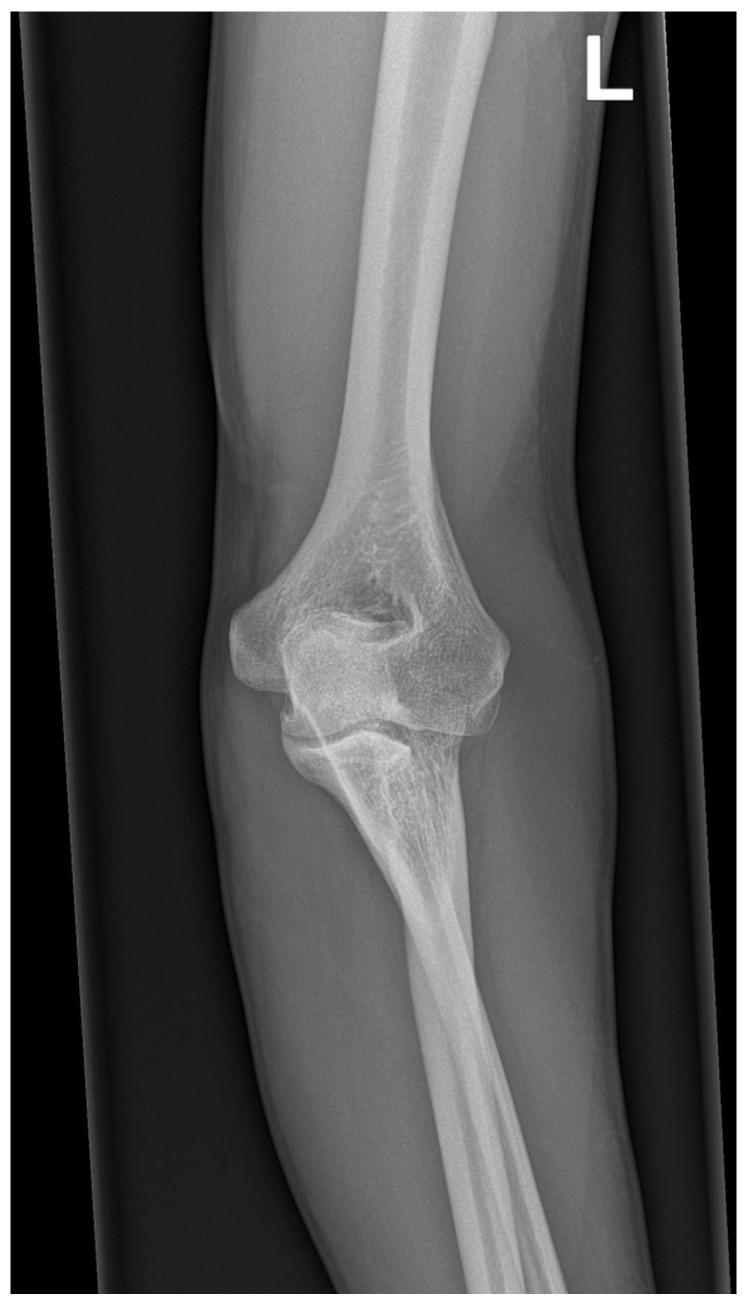

近侧桡尺骨融合(PRUS)是最常见的先天性前臂疾病,尽管其在普通人群中的患病率较低,仅有数百例报道。Pfeiffer、Poland、Holt-Oram 和其他严重的先天性综合征都包含这种异常。非综合征性病例中,孤立的 PRUS 常与 SMAD6、NOG 基因变异或性染色体非整倍体有关。一小部分伴有血液学异常的患者表现为 HOXA11 或 MECOM 基因变异。我们报告了一名非综合征性成年冰球精英运动员,其左侧前臂存在单侧近侧桡尺骨融合。在幼儿时期,他只能像右撇子一样使用曲棍球棒,并且由于缺乏旋后,直到 8 岁才确诊。X 光片显示为 Cleary-Omer Ⅲ型 PRUS,伴有桡骨头发育不良和肱尺关节轻度骨赘退行性变。由于该病症对体育活动的影响极小,因此未考虑手术干预。该运动员继续在顶级水平上从事冰球运动,并加入了国家队参加顶级比赛。问卷调查和体格检查上肢功能评估结果显示,损伤极小。受影响最大的工具是 Failla 评分,总分为 15 分,得分为 10 分。Sanger 测序的基因检测未发现 和 基因中有意义的致病性变异。通过基于阵列的比较基因组杂交未检测到潜在致病性拷贝数变异。在报告的病例中,运动员有能力应对限制前臂旋后功能的解剖变异。如今,通过不断发展的遗传学,可以全面排除更复杂的肌肉骨骼损伤和家族负担。